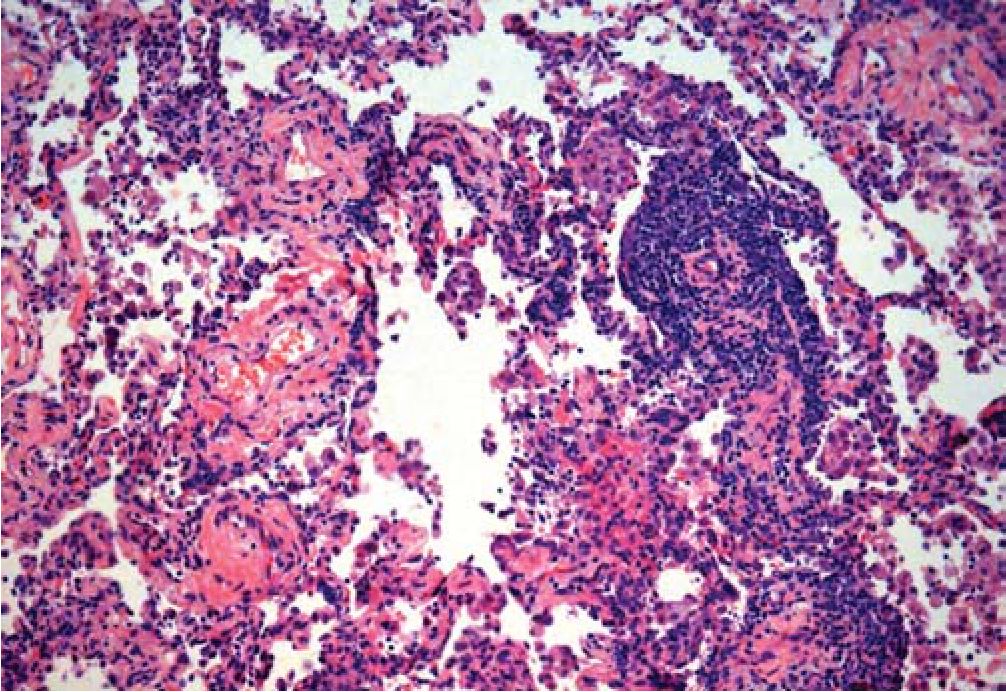

Рис. 3. Грануляционная ткань в альвеолярном ходе в сочетании с небольшим скоплением макрофагов, деформация ткани легкого.

Окраска гематоксилином и эозином. X100

Ткань легкого деформирована за счет врастания в полости альвеол и просветы части респираторных бронхиол 1-го порядка грануляционной ткани в виде полипов (рис. 2), в части полостей альвеол - скопления макрофагов с примесью эозинофилов (рис. 3) и эритроцитов с единичными эозинофилами, в других просветах альвеол - скопление фибрина с примесью эозинофилов и нейтрофилов, отдельные стенки альвеол несколько утолщена за счет небольшой лимфоцитарной инфильтрации и пролиферации альвеолоцитов 2-го типа. Фиброэластоз стенок мелких ветвей легочной артерии с сужением просветов (рис. 4).